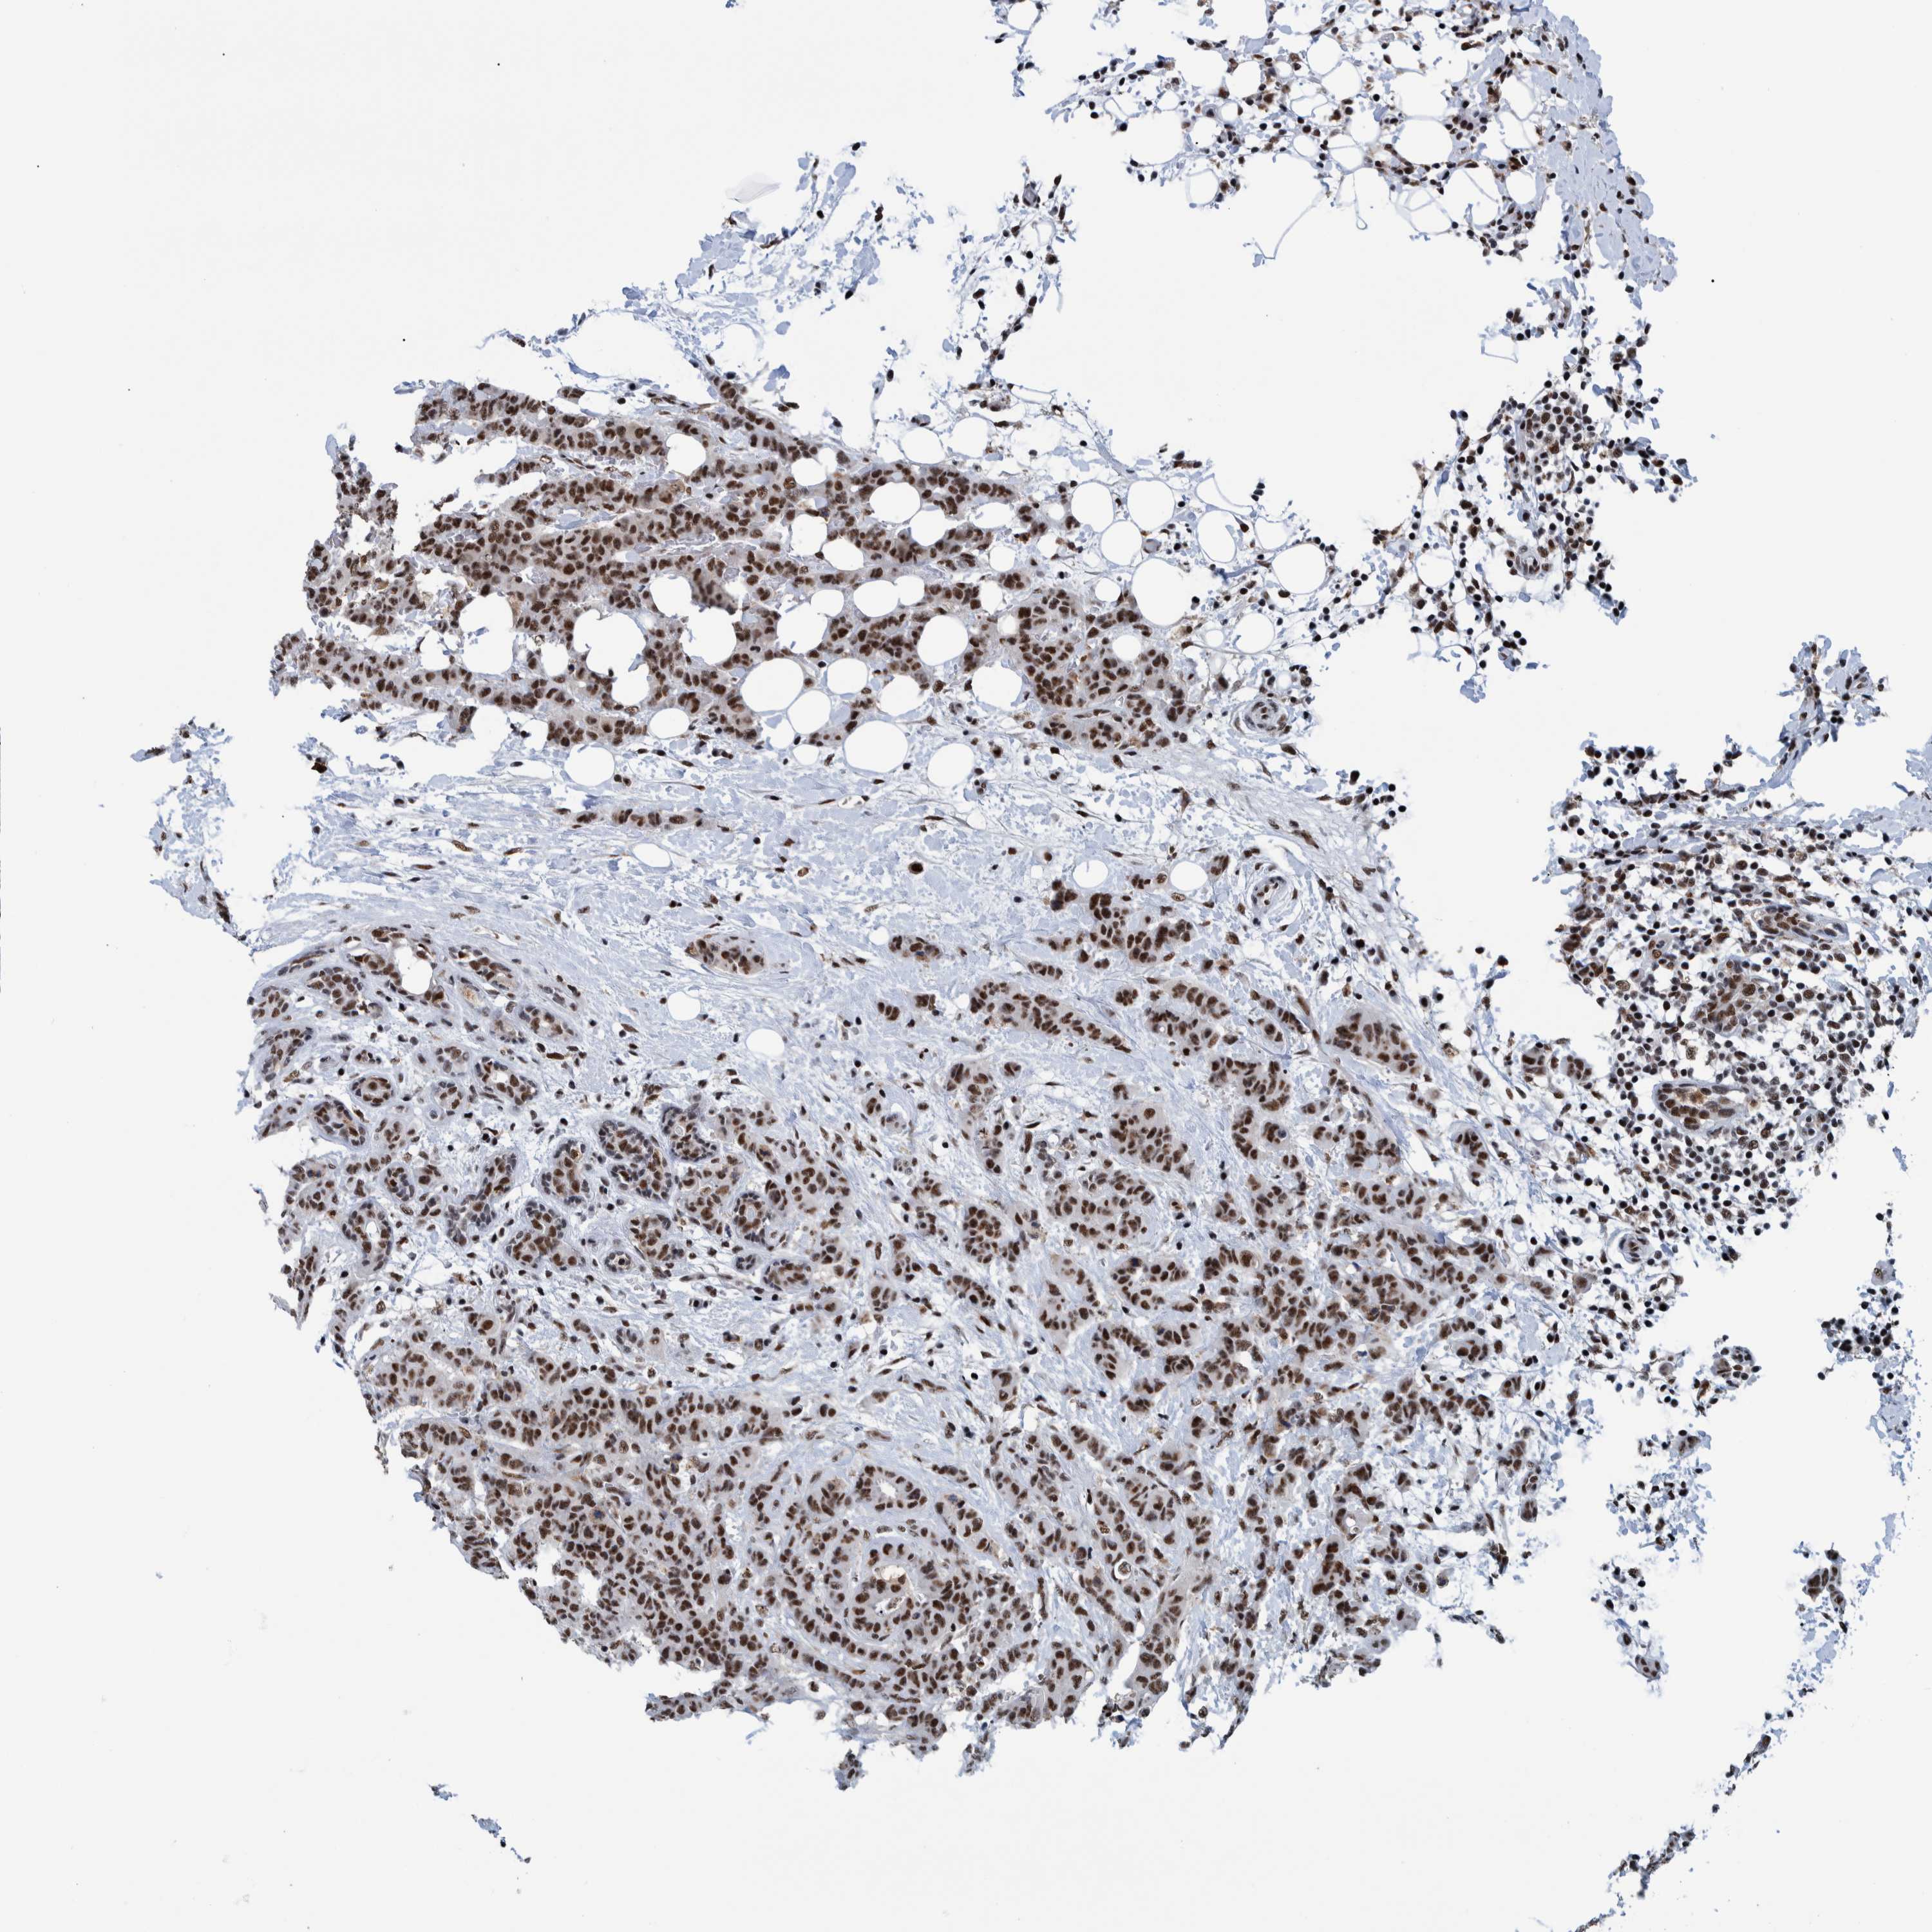

CANCER BREAST CANCER Show tissue menu

BRCA TCGA BRCA VALIDATION PROTEIN EXPRESSION